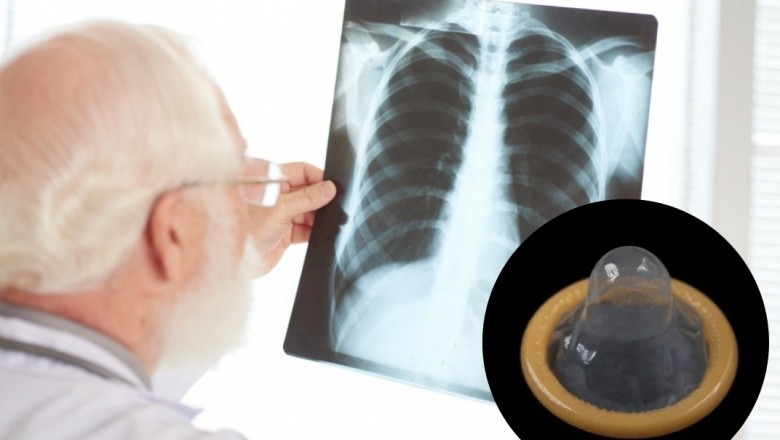

W 2004 roku w literaturze medycznej opisano nietypowy przypadek 27-letniej kobiety, która przez sześć miesięcy zmagała się z uporczywym kaszlem, odkrztuszaniem plwociny i gorączką. Objawy nie znikały mimo kolejnych prób leczenia, w tym antybiotykami oraz terapią przeciwgruźliczą.

Sprawa długo pozostawała zagadką. Dopiero wykonane później zdjęcie klatki piersiowej pokazało nieprawidłowości w obrębie prawego górnego płata płuca. Lekarze zdecydowali się wtedy na wideobronchoskopię, czyli badanie pozwalające zajrzeć do dróg oddechowych. To właśnie ono ujawniło źródło problemu - w oskrzelu znajdowała się prezerwatywa, którą następnie usunięto za pomocą sztywnej bronchoskopii i kleszczyków biopsyjnych.

Według opisu przypadku dopiero szczegółowy wywiad przeprowadzony po zabiegu potwierdził, że doszło do przypadkowego zassania prezerwatywy podczas seksu oralnego. To właśnie ten incydent miał wywołać długotrwałe problemy zdrowotne, które przez wiele miesięcy były błędnie interpretowane jako inne schorzenie układu oddechowego.

Ten przypadek pokazuje, że nawet bardzo nietypowa przyczyna może stać za objawami, które na pierwszy rzut oka wyglądają jak zwykła infekcja lub poważniejsza choroba płuc. W tym przypadku rozwiązanie zagadki zajęło aż pół roku.

To nie był jedyny taki opisany przypadek. W 2010 roku lekarze opisali historię 23-letniej kobiety, u której objawy początkowo wyglądały jak zapalenie płuc. Przez pewien czas była leczona antybiotykami, ale jej stan się nie poprawiał. Dopiero bronchoskopia wykazała prezerwatywę w prawym górnym oskrzelu. Po czasie pacjentka przypomniała sobie, że podczas seksu oralnego dostała gwałtownego ataku kaszlu - i to właśnie wtedy najprawdopodobniej doszło do aspiracji.